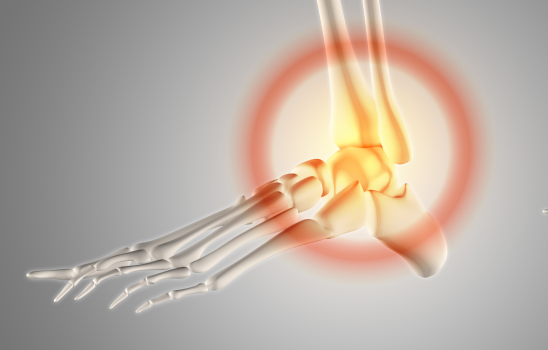

Las fracturas de tobillo son lesiones comunes que afectan a personas de todas las edades, desde atletas hasta personas mayores. En nuestro equipo, tratamos estas fracturas con frecuencia, entendiendo su impacto en la movilidad y la calidad de vida de nuestros pacientes.

Una fractura de tobillo implica la ruptura de uno o más huesos que forman la articulación del tobillo. Estos huesos son: